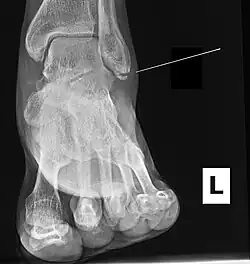

| Radiograph showing a Maisonneuve fracture of the proximal fibula | |

Ankle radiographs are used to detect widening of the tibiofibular syndesmosis or medial clear space. The medial clear space is the area between the talus of the ankle and the medial malleolus. Damage to the deltoid ligament and syndesmotic ligaments result in mortise instability, causing the talus to laterally shift and widen the medial clear space.[4][12] A clinical study, conducted in 2006 and published in the Journal of Bone and Joint Surgery, found that the medial clear space size of a normal ankle and an injured ankle measured at 4 millimetres and 5.4 millimetres in length respectively.[11] To confirm diagnosis, full-leg radiographs are used to inspect for fractures of the proximal fibula and widening of the interosseous clear space (or tibiofibular clear space). The interosseous clear space is the area between the medial side of the fibula and lateral side of the tibia. A peer-reviewed study, published in Injury in 2004, found that an interosseous clear space greater than 10 millimetres indicates diastasis of the syndesmotic ligaments.[4]

If necessary, computed tomography (CT) or magnetic resonance imaging (MRI) may also be used to clarify diagnosis. MRI scans can check for interosseous membrane or tibial tubercle damage if high instability of the ankle is diagnosed.[8][11] Arthroscopy may be used to diagnose a syndesmotic lesion but is often not recommended due to operative difficulty.[13] Stress radiographs of the ankle are used to assess the integrity of the deltoid ligament and tibiofibular syndesmosis.[9][13] The size of the medial clear space can also be measured using stress radiography.[11]